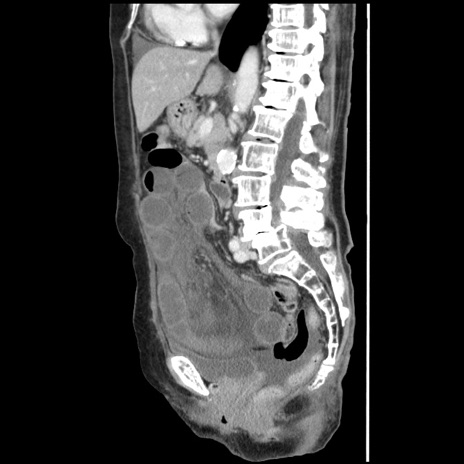

症例1(矢状断像)

【症例】80歳代女性

【主訴】腹痛

【現病歴】8時間前から腹痛あり来院。

【既往歴】糖尿病、脂質異常症、子宮体癌にて子宮全摘術

【身体所見】意識清明・会話良好だが腹痛で苦悶様、全腹部にわたって反跳痛と圧痛あり

【データ】WBC 13600、CRP 0.14、LDH 224、CK 90